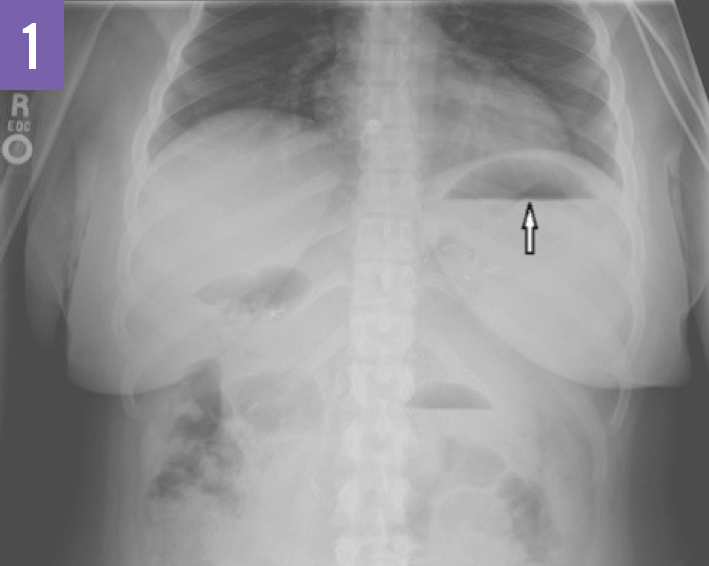

From www.researchgate.net

A chest Xray shows the presence of a gastric air bubble in the chest What Causes Air Bubbles In Rib Cage Diseases like these can damage the lungs, leaving them. Air may move from the. The air usually gets there either from the lungs or. Air trapping can occur in people with lung conditions such as asthma or chronic obstructive pulmonary disease (copd). A pneumothorax occurs when air becomes trapped between a lung and the chest wall. Buildup of air might. What Causes Air Bubbles In Rib Cage.